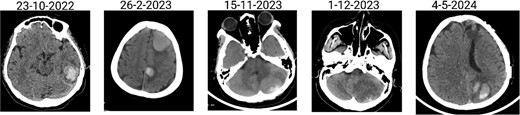

The patient has undergone multiple rounds of MRI and CT (Fig. 3) imaging examinations, the results of which have consistently shown a morphology suggestive of recurrent ICH. T2-weighted (Fig. 4) and susceptibility-weighted (SW) MRI (Fig. 5) showed many cerebral cavernous malformations (CCMs) scattered across both cerebral hemispheres, mainly located in the left parietal, frontal, and occipital lobes, with some lesions extending into the brainstem. Multiple lesions presented with a mixed signal intensity corresponding to different stages of haemorrhage and blood degradation products. There was noticeable hemosiderin deposition, indicating the presence of chronic microhaemorrhages. These deposits were particularly extensive in the left parietal lobe, corresponding to the site of the largest and most symptomatic haemorrhage. Regions of gliosis were observed near the haemorrhagic lesions, indicating long-term damage from previous haemorrhages. SWI confirmed the presence of multiple microhaemorrhagic lesions in the parenchyma and subcortical white matter, complicating the clinical picture.

Brain CT scan showing multiple previous haemorrhagic lesions in the brain parenchyma with evidence of chronicity.